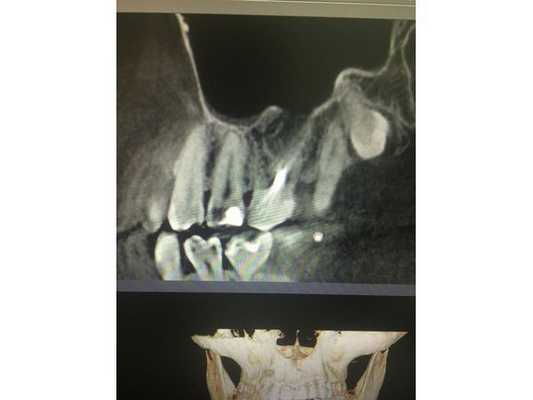

По данным компьютерной томограммы, в зубе три канала, тень пломбировочного материала определяется на всём протяжении каналов в виде непрерывной линейной структуры, рентгенологически верхушки корней зуба обтурированы, т. е. закрыты.

Обнаружен дополнительный канал со стороны щеки, содержимое канала не просматривается. В области нёбного канала видна тень металлической плотности, по конфигурации она соответствует анкерному штифту.

В области верхушек корней визуально определяется деструкция (разрушение) кости без чётких контуров. Плотность участка разрушения снижена, характерный костный рисунок частично сохранён. Область разрушения частично затрагивает альвеолярную бухту гайморовой пазухи. Кортикальная пластинка, отделяющая гайморову пазуху от зубов, в проекции деструкции прослеживается фрагментарно.